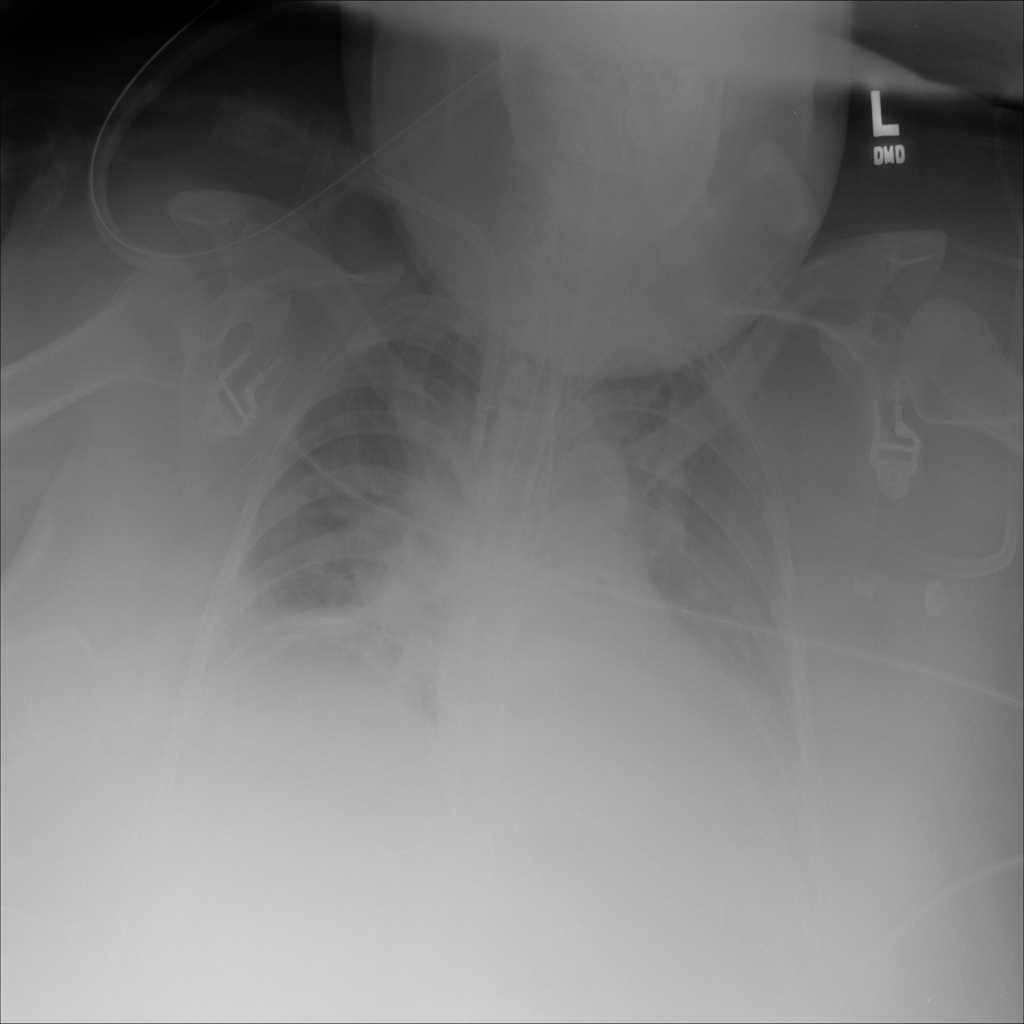

PAT-DB80 · IMG-000Atelectasis

PAT-DB80 · IMG-000

PA